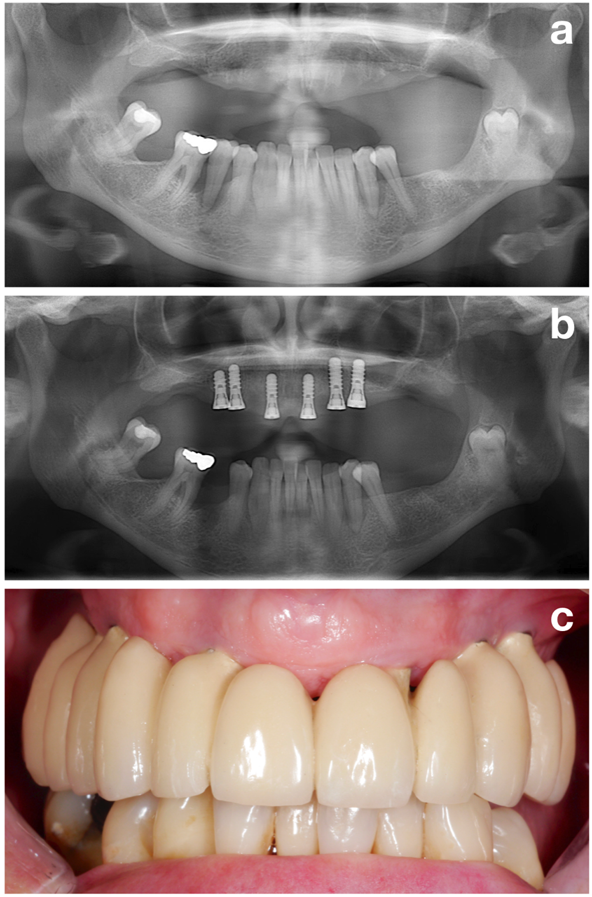

Figure 2. Il convient d'établir une situation parodontale stable avant l’implantation. Un patient avant le traitement parodontal (a), après le traitement parodontal et l'implantation (b), et après la restauration prothétique (c). © Dr K. Bertl

La première phase (c’est-à-dire le prétraitement) a pour but de préparer le patient de façon optimale en vue de l’implantation en évaluant tous les facteurs de risque potentiels mais en ciblant l’un des objectifs plus importants, à savoir l’établissement d’une situation parodontale stable (Figure 2).